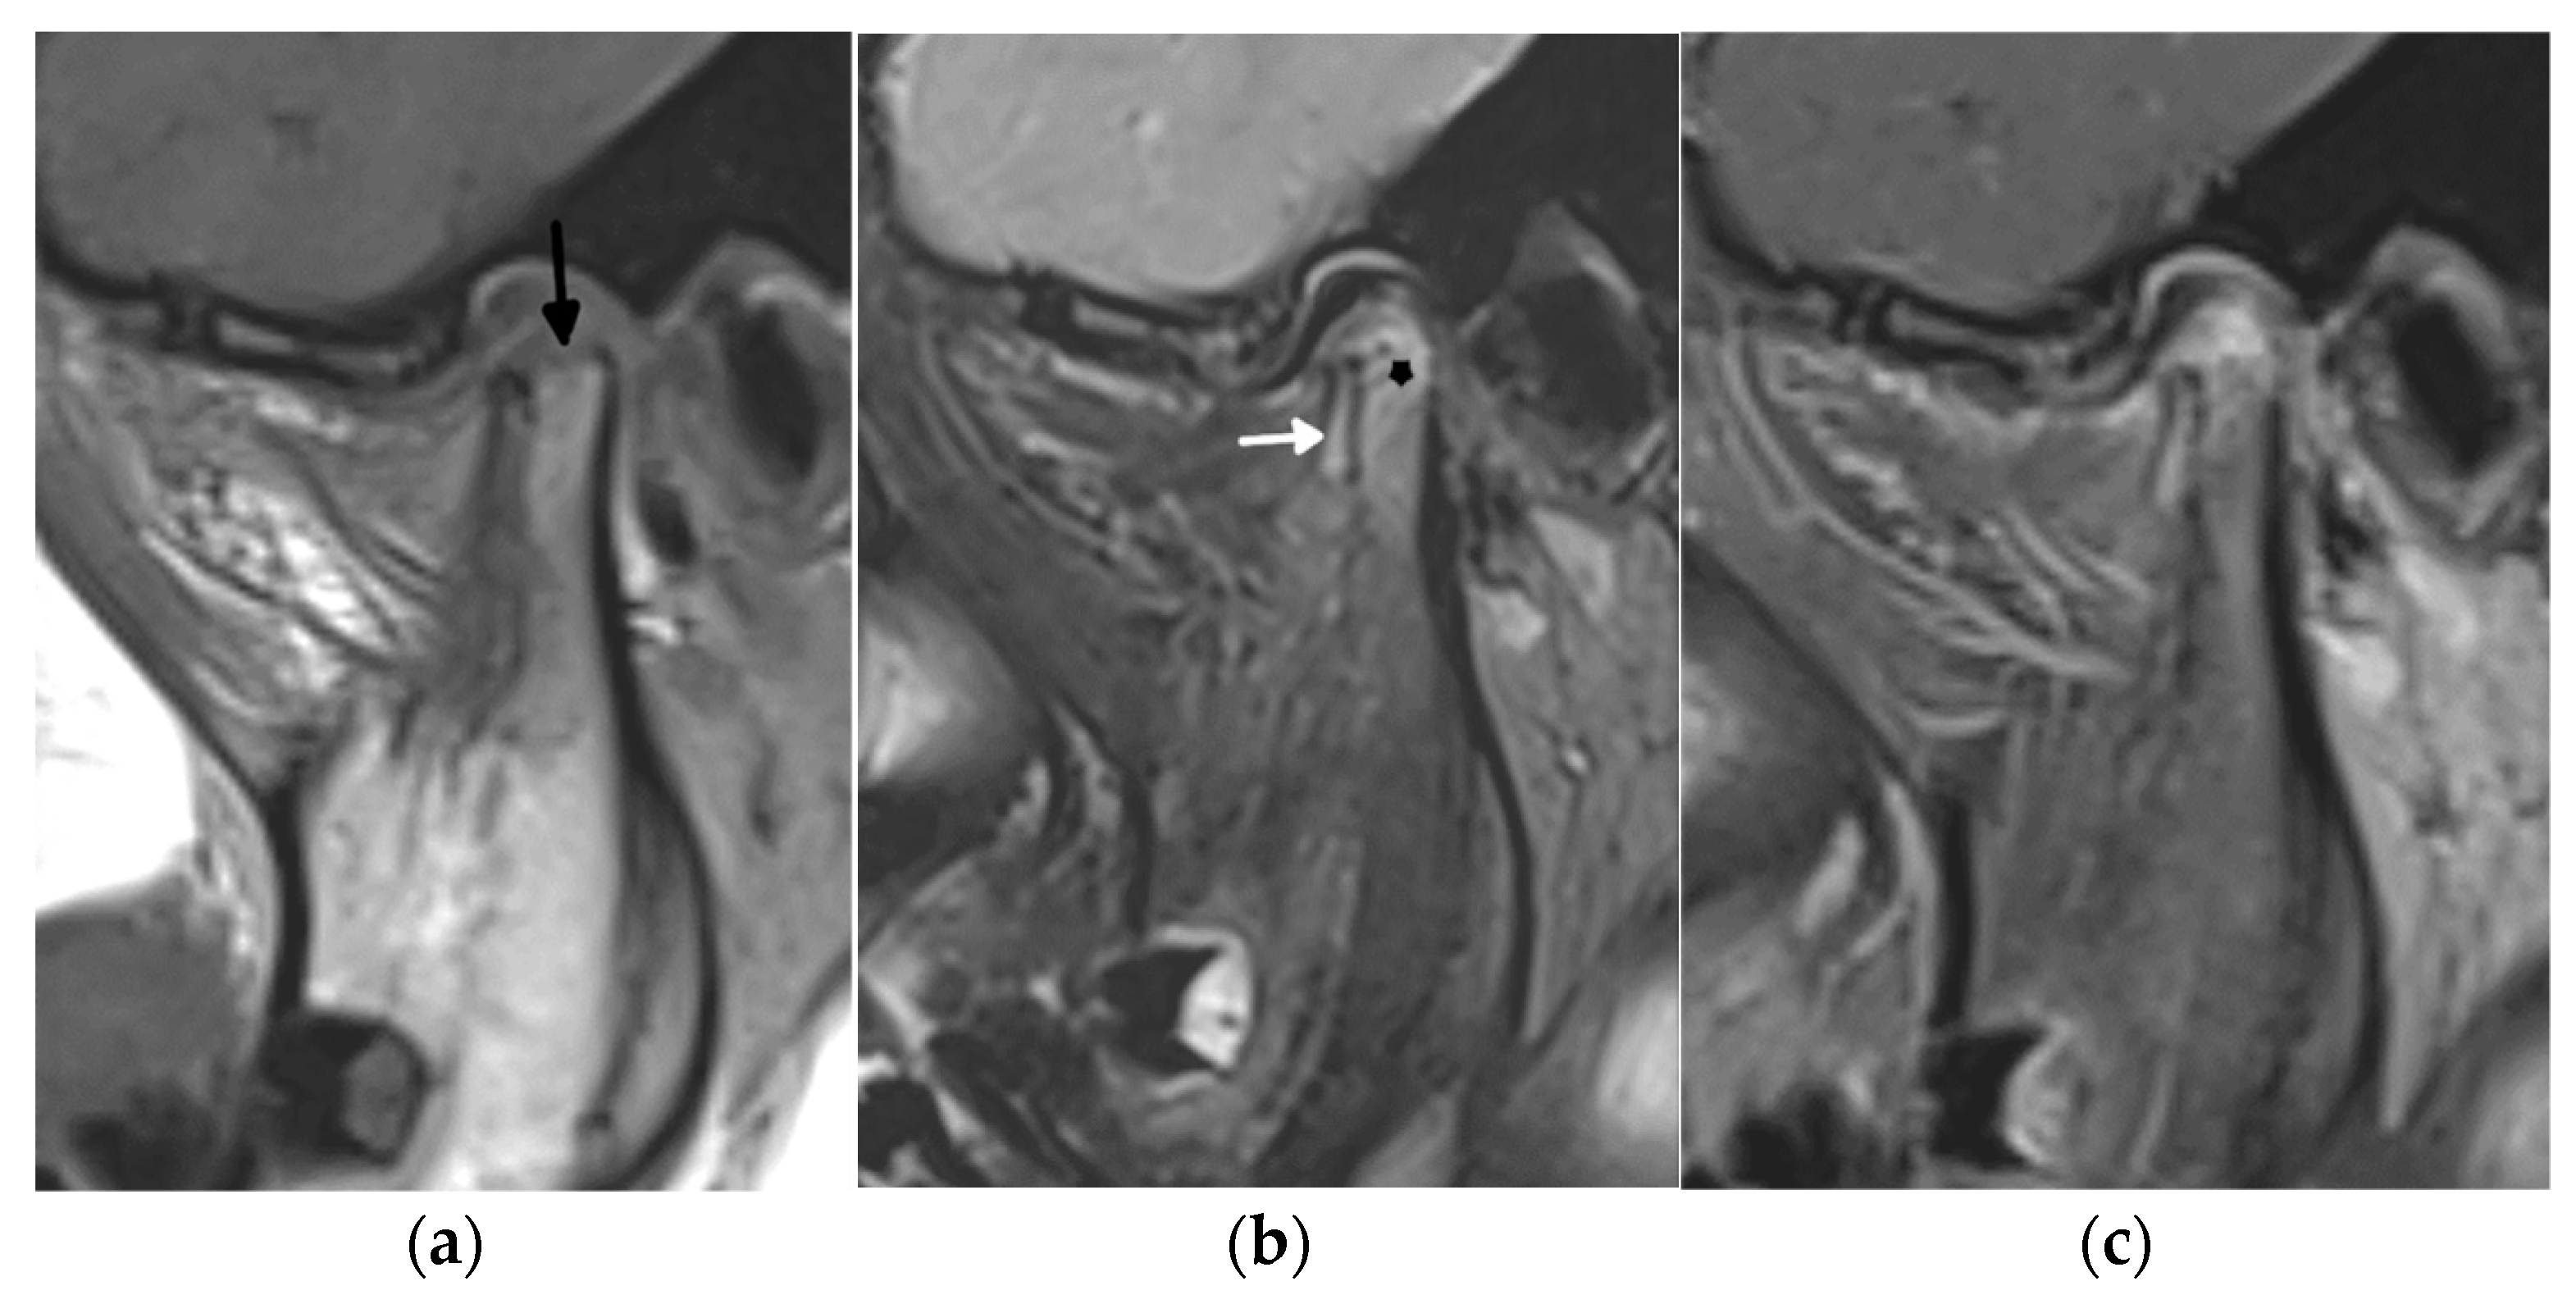

- Stoll, M.L.; Kau, C.H.; Waite, P.D.; Cron, R.Q. Temporomandibular joint arthritis in juvenile idiopathic arthritis, now what? Pediatr. Rheumatol. Online J. 2018, 16, 32. [Google Scholar] [CrossRef]

- Angenete, O.W.; Augdal, T.A.; Rygg, M.; Rosendahl, K. MRI in the Assessment of TMJ-Arthritis in Children with JIA; Repeatability of a Newly Devised Scoring System. Acad. Radiol. 2021, 29, 1362–1377. [Google Scholar] [CrossRef]

- Tolend, M.A.; Twilt, M.; Cron, R.Q.; Tzaribachev, N.; Guleria, S.; von Kalle, T.; Koos, B.; Miller, E.; Stimec, J.; Vaid, Y.; et al. Toward Establishing a Standardized Magnetic Resonance Imaging Scoring System for Temporomandibular Joints in Juvenile Idiopathic Arthritis. Arthritis Care Res. 2018, 70, 758–767. [Google Scholar] [CrossRef]

- Tolend, M.; Doria, A.S.; Meyers, A.B.; Larheim, T.A.; Abramowicz, S.; Aguet, J.; Appenzeller, S.; Arvidsson, L.Z.; Averill, L.W.; Feldman, B.M.; et al. Assessing the Reliability of the OMERACT Juvenile Idiopathic Arthritis Magnetic Resonance Scoring System for Temporomandibular Joints (JAMRIS-TMJ). J. Clin. Med. 2021, 10, 4047. [Google Scholar] [CrossRef]

- Kirkhus, E.; Gunderson, R.B.; Smith, H.J.; Flato, B.; Hetlevik, S.O.; Larheim, T.; Arvidsson, L. Temporomandibular joint involvement in childhood arthritis: Comparison of ultrasonography-assessed capsular width and MRI-assessed synovitis. Dentomaxillofac Radiol. 2016, 45, 20160195. [Google Scholar] [CrossRef]

- Hechler, B.L.; Phero, J.A.; van Mater, H.; Matthews, N.S. Ultrasound versus magnetic resonance imaging of the temporomandibular joint in juvenile idiopathic arthritis: A systematic review. Int. J. Oral Maxillofac. Surg. 2018, 47, 83–89. [Google Scholar] [CrossRef]

- Clemente, E.J.I.; Tolend, M.; Junhasavasdikul, T.; Stimec, J.; Tzaribachev, N.; Koos, B.; Spiegel, L.; Moineddin, R.; Doria, A.S. Qualitative and semi-quantitative assessment of temporomandibular joint MRI protocols for juvenile idiopathic arthritis at 1.5 and 3.0T. Eur. J. Radiol. 2018, 98, 90–99. [Google Scholar] [CrossRef]